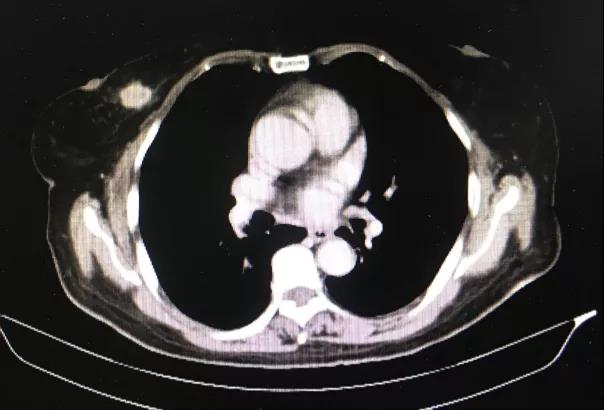

一个人生病时,回想这一生,什么对他来说最重要呢? 2020年,是马先生抗争病魔的第5个年头。 “我老公是15年12月份...